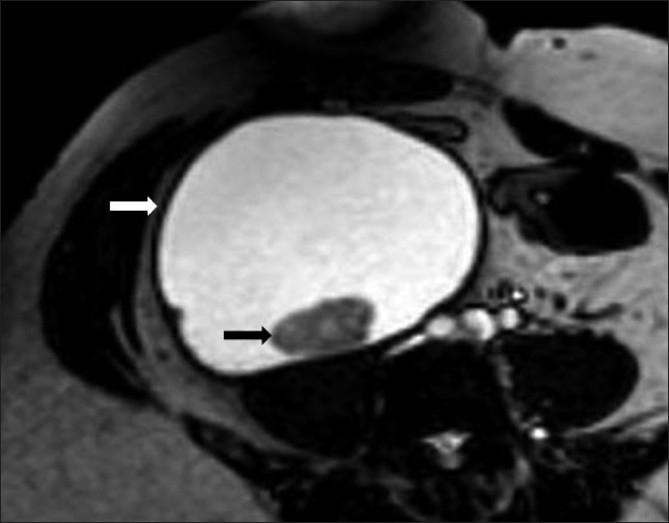

病例报告:以腹腔内囊肿形式出现的丝虫病。

Case report: Filariasis presenting as an intra-abdominal cyst.

Filariasis is an endemic infection seen in the tropical and subtropical regions of the world, presenting with lymphatic dysfunction in the form of lymphocele, hydrocele, chyluria, or groin lymphadenovarix. We report a rare presentation of filariasis as an intra-abdominal cystic mass.

丝虫病是一种在世界热带和亚热带地区流行的感染性疾病,表现为淋巴管功能障碍,形式有淋巴囊肿、鞘膜积液、乳糜尿或腹股沟淋巴管曲张。我们报告了一例罕见的丝虫病表现为腹腔内囊性肿块。